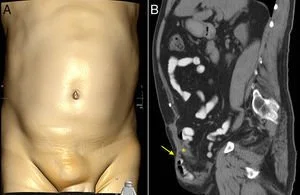

Los defectos de la pared abdominal son aberturas o áreas debilitadas en los músculos y tejidos que rodean la cavidad abdominal, lo que puede permitir que los órganos sobresalgan, formando una hernia. Estos defectos pueden ser congénitos (presentes al nacer) o adquiridos, y pueden variar en tamaño y gravedad.

Los defectos adquiridos grandes de pared abdominal, también conocidos como hernias ventrales adquiridas o eventraciones, son protrusiones de órganos abdominales a través de una abertura o debilitamiento en la pared abdominal, que ocurre después del nacimiento, a diferencia de los defectos congénitos. Estas aberturas pueden ser resultado de cirugías previas, traumatismos, o debilidad muscular asociada a obesidad.

La cirugía de reconstrucción de pared abdominal en defectos adquiridos está indicada cuando existen hernias complejas, eventraciones, defectos de cierre de pared abdominal post-quirúrgicos, o cuando hay pérdida de la integridad de la pared abdominal debido a secuelas de traumatismos, tumores o infecciones. También se considera en casos de diástasis abdominal severa, especialmente si hay problemas funcionales.